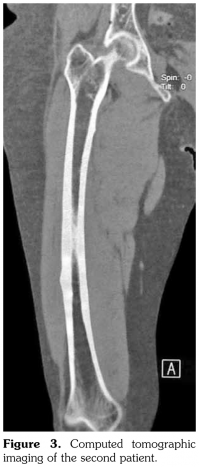

Case 1– A 73-year-old female patient presented with low back, knee, and anterior thigh pain. Pain severity was 8 over 10 point according to visual analog scale. She had difficulty in walking because of pain. She had a history of arthroscopic knee surgery for meniscal pathology in her left knee five years ago. She had chronic low back pain due to L4-5 disc herniation and lumbar spinal stenosis. She had been treated for osteoporosis with alendronate for two years, then with salmon calcitonin for two years and ibandronic acid for a year. Neurological examination was normal. Plain radiographs revealed bilateral lateral cortical thickening in the femur (Figure 1). Magnetic resonance imaging was done to rule out fracture. Bone scintigraphy showed increased uptake in bilateral femoral diaphysis. Routine biochemical tests were normal except increased urinary deoxypyridinoline. Urinary deoxypyridinoline level was 63 nM/mMCre (normal range: 3-7.4 nM/mMCre).

Typical femoral periosteal stress reaction was described as cortical thickening in the lateral side of the subtrochanteric region. In addition, Kwek et al.(5) found bilateral findings of stress reactions or fractures on plain radiographs in 53% of patients on bisphosphonate therapy. In both of our patients, we observed cortical stress reaction bilaterally.

Radiologically, femoral periosteal stress reaction is described as the presence of the dreaded black line which is a transverse black line traversing the cortex that can be complete or incomplete.(6-9) Magnetic resonance imaging findings of femoral periosteal stress reaction include focal cortical thickening, bone edema, focal cortical resorption cavities and dreaded black line. There is an association between radiographic findings and the presence of clinical symptoms.(10) Similarly, our patients had thigh pain and difficulty in walking.